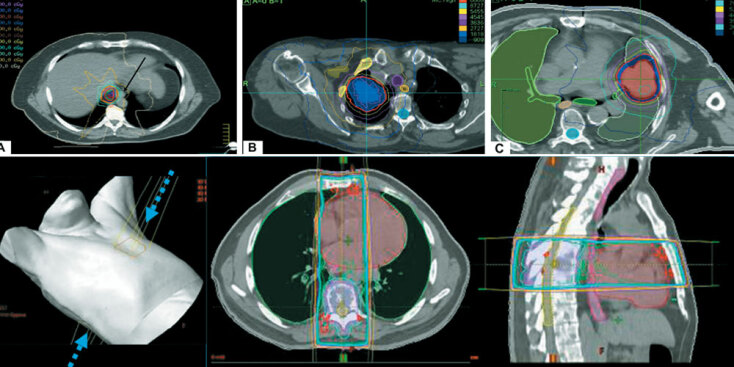

Έτσι, η Στερεοτακτική Ακτινοχειρουργική αποτελεί ένα από τα κύρια όπλα στη φαρέτρα αντιμετώπισης του καρκίνου. Είναι ένα αναίμακτο χειρουργείο, χωρίς καμία τομή, αναισθησία ή νοσοκομειακή παραμονή. Φέρει τη λογική μιας χειρουργικής επέμβασης, χρησιμοποιώντας την ακτινοβολία για την πρόκληση βλάβης στον όγκο, με ισοδύναμη αποτελεσματικότητα.

Οι υψηλές δόσεις ακτινοβολίας της τεχνικής χορηγούνται με τέτοια ακρίβεια, που εξασφαλίζουν τη μέγιστη δυνατή προστασία των γύρω φυσιολογικών ιστών, με αποτέλεσμα το χαμηλό ρίσκο παρενεργειών συγκρινόμενη με το κλασικό χειρουργείο ή άλλες τοπικές θεραπείες. Παράλληλα, η χρήση ιοντίζουσας ακτινοβολίας δημιουργεί μη επιδιορθώσιμες βλάβες στο DNA των βλαφθέντων κυττάρων, ώστε να μην μπορούν να αναπαραχθούν και να μεγαλώσουν περαιτέρω. Ο μη φυσιολογικός ιστός καθίσταται ανενεργός και υφίσταται σταδιακή σμίκρυνση.

Στο σώμα, όπου καλείται στερεοτακτική ακτινοθεραπεία σώματος, εφαρμόζεται για την αντιμετώπιση κακοηθειών σε οποιοδήποτε σημείο, ενώ έχει βρει και εφαρμογή στην καρδιολογία (καρδιακή αρρυθμία). Η θεραπευτική μέθοδος επιβάλλεται να γίνεται μόνο σε εξειδικευμένα κέντρα από ομάδα ειδικευμένων ιατρών, ιατρών φυσικής ιατρικής και τεχνολόγων ακτινοθεραπείας.